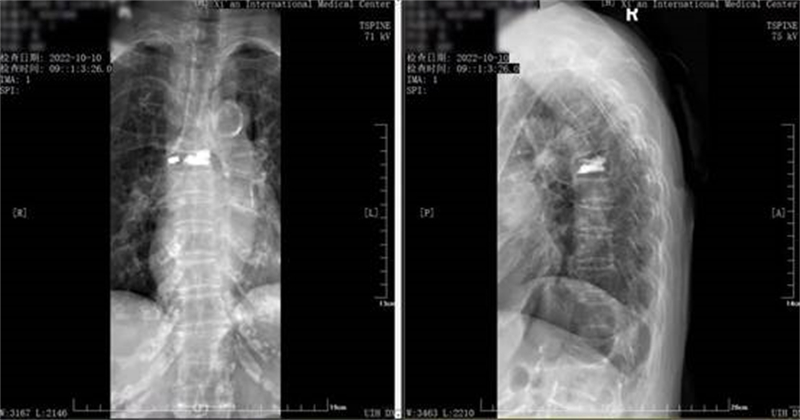

与家属沟通达成统一意见后,贺西京院长带领张伟、吴卓等医生,在麻醉医师何家璇的护航下,为李奶奶做了“胸6椎体骨质疏松性压缩性骨折后路经皮椎体后凸成形术”。整个手术过程在C臂透视下完成,手术时间仅用了30分钟。

由于是精细的微创手术,李奶奶的手术切口只有3毫米,术中出血仅5毫升,所以恢复得特别好。术后当天,她就能拄着拐杖下地、走路了。术后第二天,李奶奶就感觉腰背部不疼了。“我能走!现在不疼了,感觉好着呢!”说着,她就拿起自己的拐杖利索地在病房里走了好几个来回。鉴于李奶奶各项指标稳定且恢复良好,术后第二天就办理了出院。